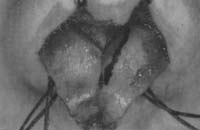

The area between the medial crura is dissected to create a pocket to place the strut. The rect angular cartilage strut typically measures 8 mm to 12 nun in length, 3 mm to 4 min in width, and 1 4 n 4 n to 2 4 nm in thickness. The strut is most typically fashioned from harvested septal cartilage, but also, when necessary, from auricular cartilage, and at times from rib cartilage. The strut is positioned so that it sits above (without extending to) the nasal spine (Fig. 1). It is preferable to leave a small soft-tissue pad between the strut and the nasal spine. The strut should not extend above the intermediate crura. It is secured to the medial crura with several absorbable mattress sutures (e.g., 4-0 plain gut, Keith needle) placed through the vestibular skin. Asymmetries of the lower lateral cartilage (LLC) may be improved with placement of the strut (Fig. 2). Asymmetry of the tip may be created if the medial crura are asymmetrically sutured to the strut (Fig. 3), or if an overlong shut extending beyond the nasal spine shifts to the side of the nasal spine, thereby causing a deviated nasal tip (Fig. 3) (1,2).

Figure 1. Placement of columellar strut. A, B: The strut sits above (without extending to) the nasal spine, and it should not extend above the intermediate crura. A columellar strut may be placed via the external rhinoplasty approach. With proper exposure achieved, dissection of a pocket between the medial crura is undertaken. The carved columellar strut is placed in the pocket, as described earlier and secured with interrupted 4-0 plain gut on a straight septal (Keith) needle.

Figure 2. A—D: Asymmetries of the lower lateral cartilage may be improved with placement of the strut.